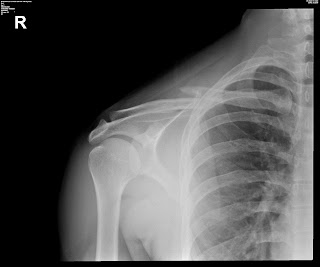

An avulsion fracture is a bone fracture which occurs when a fragment of bone tears away from the main mass of bone as a result of physical trauma. Long bone growth plate oblique fracture avulsion fracture functions of the skeletal system ball and socket joint. The patient began using a normal shoe at 10 weeks and resumed his running. An avulsion fracture is when a small piece of bone breaks and pulls away from a larger bone. Related online courses on physioplus. Learn how most avulsion fractures are treated. This typically involves the separation of the posterior tibial insertion of the pcl to variable d. This information will guide you through the next 6 weeks of your rehabilitation. In rigid shoe waiting for ortho consult. An avulsion fracture is a bone fracture which occurs when a fragment of bone tears away from the main mass of bone as a result of physical highly trained athletes can overcome this neurological inhibition of strength and produce a much greater force output capable of breaking or avulsing a bone. Part or all of the piece may break away. An avulsion fracture is also sometimes called a ballerina fracture or dancer's fracture because of the pointe position that ballet dancers. During an avulsion injury, a small fragment of bone at the base of the 5th metatarsal is pulled off by a strong ligament that is attached to this part of the bone. Avulsion fractures of the hip and. Great toe injury is common in athletes. Dx displaced avulsion fracture, base of big toe after worsening forefoot pain. While this might sound scary, these fractures are actually very easy to treat in most cases.